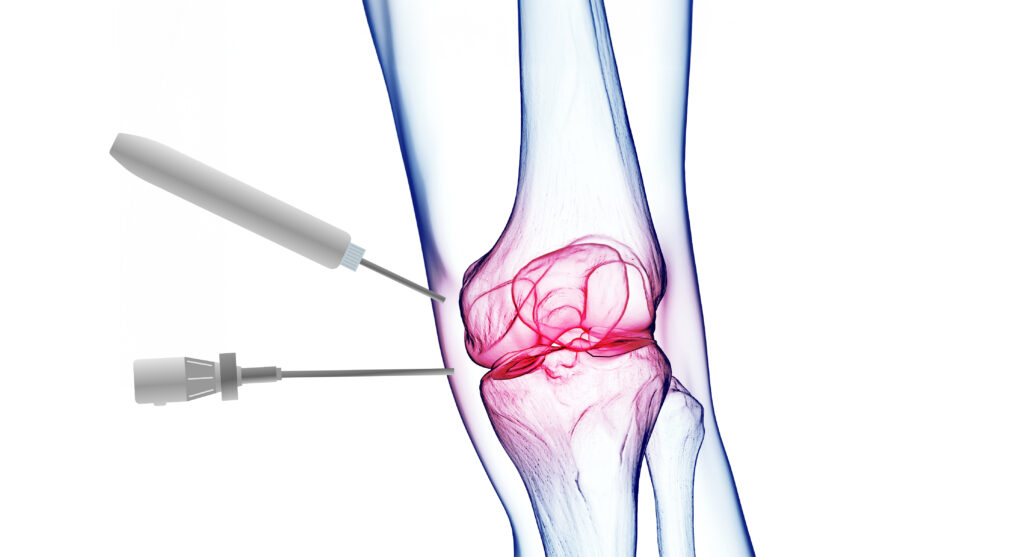

Το πεδίο εξειδίκευσης του γιατρού περιλαμβάνει τις πιο σύγχρονες χειρουργικές τεχνικές

EXCELLENT Based on 289 reviews Posted on Panos LoukasTrustindex verifies that the original source of the review is Google. Η επέμβαση που έκανα στον ώμο ήταν επιτυχημένη, ο γιατρός πολύ επεξηγηματικός και υποστηρικτικός και πάντα διαθέσιμος!Posted on Σάββας ΚοτρικηςTrustindex verifies that the original source of the review is Google. Ευχαριστώ πολύ τον γιατρό Ιωάννη Πολυζωη γιατί μετά από ένα δύσκολο χειρουργείο ολικής αρθροπλαστικης ώμου, είμαι σε άριστη κατάσταση.Posted on Eleni RizouTrustindex verifies that the original source of the review is Google. Υποβλήθηκα σε αρθροσκόπηση ώμου από τον κ. Πολυζώη και η εμπειρία ξεπέρασε κάθε προσδοκία. Πρόκειται για έναν εξαιρετικό χειρουργό, με κορυφαία επιστημονική κατάρτιση. Από την πρώτη στιγμή με αντιμετώπισε με σεβασμό, ειλικρίνεια και πραγματικό ενδιαφέρον, εξηγώντας με σαφήνεια όλες τις λεπτομέρειες της πάθησης και της επέμβασης. Η αρθροσκόπηση πραγματοποιήθηκε με απόλυτη επιτυχία, χωρίς καμία επιπλοκή, και η ανάρρωση ήταν εντυπωσιακά γρήγορη. Τον συστήνω ανεπιφύλακτα ως έναν από τους καλύτερους ορθοπεδικούς χειρουργούς με κορυφαία κατάρτιση και εμπειρία.Posted on Marianna AggelakiTrustindex verifies that the original source of the review is Google. Καταπληκτικός γιατρός,εξαιρετικός άνθρωπος . Προσιτός στον ασθενή με φοβερές γνώσεις και εμπειρία.Απο προσωπική εμπειρία πριν λίγες μέρες με σοβαρό πρόβλημα στον ώμο μου η αντιμετώπιση ήταν άμεση και το αποτέλεσμα της αποκατάστασης πολύ γρήγορο. Ευχαριστώ πολύ κ.Πολυζωη!!!!!Posted on DT TseTrustindex verifies that the original source of the review is Google. Εξαιρετικός ορθοπεδικός χειρουργός! Έπαθα ρίξη στους τέντοντες του αριστερού ώμου και τότε μου συνέστησαν τον Δρ. Ιωάννη Πολυζώη. Έπειτα απο τις απαραίτητες εξετάσεις και αφού μου εξήγησε τι ακριβώς πρέπει να γίνει, υποβλήθηκα σε αρθροσκόπηση με συρραφή των τενόντων και η εμπειρία μου ήταν άψογη από την αρχή μέχρι το τέλος. Ο Δρ. Ιωάννης Πολυζώης, Χειρούργος Ορθοπεδικός, έδειξε επαγγελματισμό, ανθρωπιά και πραγματικό ενδιαφέρον για την αποκατάστασή μου. Μου εξήγησε αναλυτικά την διαδικασία, με έκανε να αισθανθώ ασφαλής και το αποτέλεσμα του χειρουργείου ήταν εξαιρετικό. Η αποθεραπεία κύλησε ομαλά χάρη στις σαφείς οδηγίες του και την άμεση ανταπόκριση σε κάθε μου απορία. Είχε πάντα συνεχή επικοινωνία μαζί μου αλλά και με τον φυσιοθεραπευτή μου, για την καλύτερη προσέγγιση στην αποκατάστασή μου. Αξίζει επίσης να αναφέρω πως το ιατρείο του είναι υπερσύγχρονο και πλήρως εξοπλισμένο. Από την πρώτη στιγμή ένιωσα ότι βρίσκομαι σε καλά χέρια, σε ένα περιβάλλον που εμπνέει εμπιστοσύνη και επαγγελματισμό. Τον συνιστώ ανεπιφύλακτα σε όποιον αναζητά έναν αξιόπιστο και έμπειρο χειρούργο ορθοπεδικό!Posted on Stefanos TogoussidisTrustindex verifies that the original source of the review is Google. Εξαιρετικός ως επιστημών και ως άνθρωπος . Είχα απόλυτη επιτυχία στην άρθρο πλαστική ωμού και νιώθω τέλεια Νομίζω ότι ο κ. Πολυζώης θα πρέπει είναι σημείο αναφοράς Ένα τόνο μετά την πρώτη αναστροφή ολική Άρθρο πλαστική στον αριστερό μου ώμο πήρα απόφαση να κάνω και στον δεξί μου ώμο το ίδιο . Πήγα στον κ Πολυζώη τον εξαιρετικό γιατρό επιστήμονα αλλά πάνω από όλα άνθρωπο να αναλάβει το δύσκολο αυτό έργο με δεδομένο ότι ο ώμος μου είχε και μια κλήση που έκανε τα πράγματα πολύ πιο δύσκολα. Το αποτέλεσμα όπως αναμένονταν εξαιρετικό. Λίγες εβδομάδες μετά ο ώμος μου είναι σε εξαιρετική κατάσταση. Χάρι στον κ Ι Πολυζώη έχω 2 ώμους σε τέλεια κατάσταση χωρίς πόνους και λειτουργικούς. Πραγματικά ότι και να πεις για τον Ι Πολυζώη τον επιστήμονα τον γιατρό τον άνθρωπο που σε βλέπει σαν α είσαι φίλος του από πάλαια και θέλει να προσφέρει όλες τις γνώσεις του κσι την εμπειρία του για να σε βοηθήσει του αξίζει ένα μεγάλο ευχαριστώ να είναι πάντα καλά. Τέλος θα πω κάτι που πραγματικά πιστεύω πρέπει να γίνει το σημείο αναφοράς όσον αφορά τους ώμους και άνω άκρα Μακάρι να είχαμε και άλλους σαν τον Ι Πολυζώη θα νοιθωθαμε όλοι ασφάλεια και σιγουριά εγώ σε ευχαριστώ πολυ από τα βάθη της καρδιάς μου !!Posted on Σωτήρης ΓκούνηςTrustindex verifies that the original source of the review is Google. Φιλικος και καταρτισμενος γιατρος!Posted on Gabriele PinzoneTrustindex verifies that the original source of the review is Google. We are very happy to have chosen Dr. Polyzois for a problem at the leg of my wife: he is very professional but he was also very friendly and helpful since the very first phone call. As Expats just relocated in Greece we have even more appreciate these qualities along with his excellent English!Posted on Stathis TsamtsourisTrustindex verifies that the original source of the review is Google. Εξαιρετικός γιατρός πραγματοποίησε άψογη εκτέλεση εργασίας σε σοβαρό πρόβλημα στο ώμο σου εμπνέει εμπιστοσύνη και σαν γιατρός και σαν άνθρωποςPosted on Eleni KourtTrustindex verifies that the original source of the review is Google. Είχα την τύχη να επισκεφθώ τον κ. Πολυζώη για ένα ορθοπεδικό πρόβλημα που με ταλαιπωρούσε και πραγματικά έμεινα εντυπωσιασμένη από το επίπεδο επαγγελματισμού του. Από την πρώτη στιγμή έδειξε προσοχή, ευγένεια και διάθεση να ακούσει προσεκτικά τα συμπτώματά μου. Η εξέταση ήταν λεπτομερής και κατανοητή, με σαφείς εξηγήσεις για την αιτία του προβλήματος και τις διαθέσιμες επιλογές θεραπείας. Με έκανε να αισθανθώ σιγουριά και εμπιστοσύνη, καθώς φαινόταν ξεκάθαρα ότι γνωρίζει σε βάθος το αντικείμενο του. Όσες φορές κι αν τον κάλεσα, όσες φορές κι αν χρειάστηκε να τον επισκεφθώ ή να ζητήσω βοήθεια, ήταν πάντα πρόθυμος και διαθέσιμος να με εξυπηρετήσει. Με υπομονή και επαγγελματισμό μου εξηγούσε κάθε λεπτομέρεια, ώστε να καταλαβαίνω ακριβώς τι συμβαίνει και πώς θα προχωρήσουμε. Η επικοινωνία ήταν άψογη, η φροντίδα ανθρώπινη και η αντιμετώπιση εξατομικευμένη, προσαρμοσμένη στις ανάγκες μου. Τον συστήνω ανεπιφύλακτα σε όποιον αναζητά έναν εξαιρετικό γιατρό με επιστημονική κατάρτιση, επαγγελματική συνέπεια και πραγματικό ενδιαφέρον για τον ασθενή.